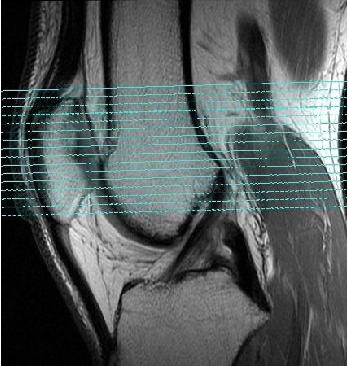

Figure 1. Standard axial slice prescription off a sagittal image